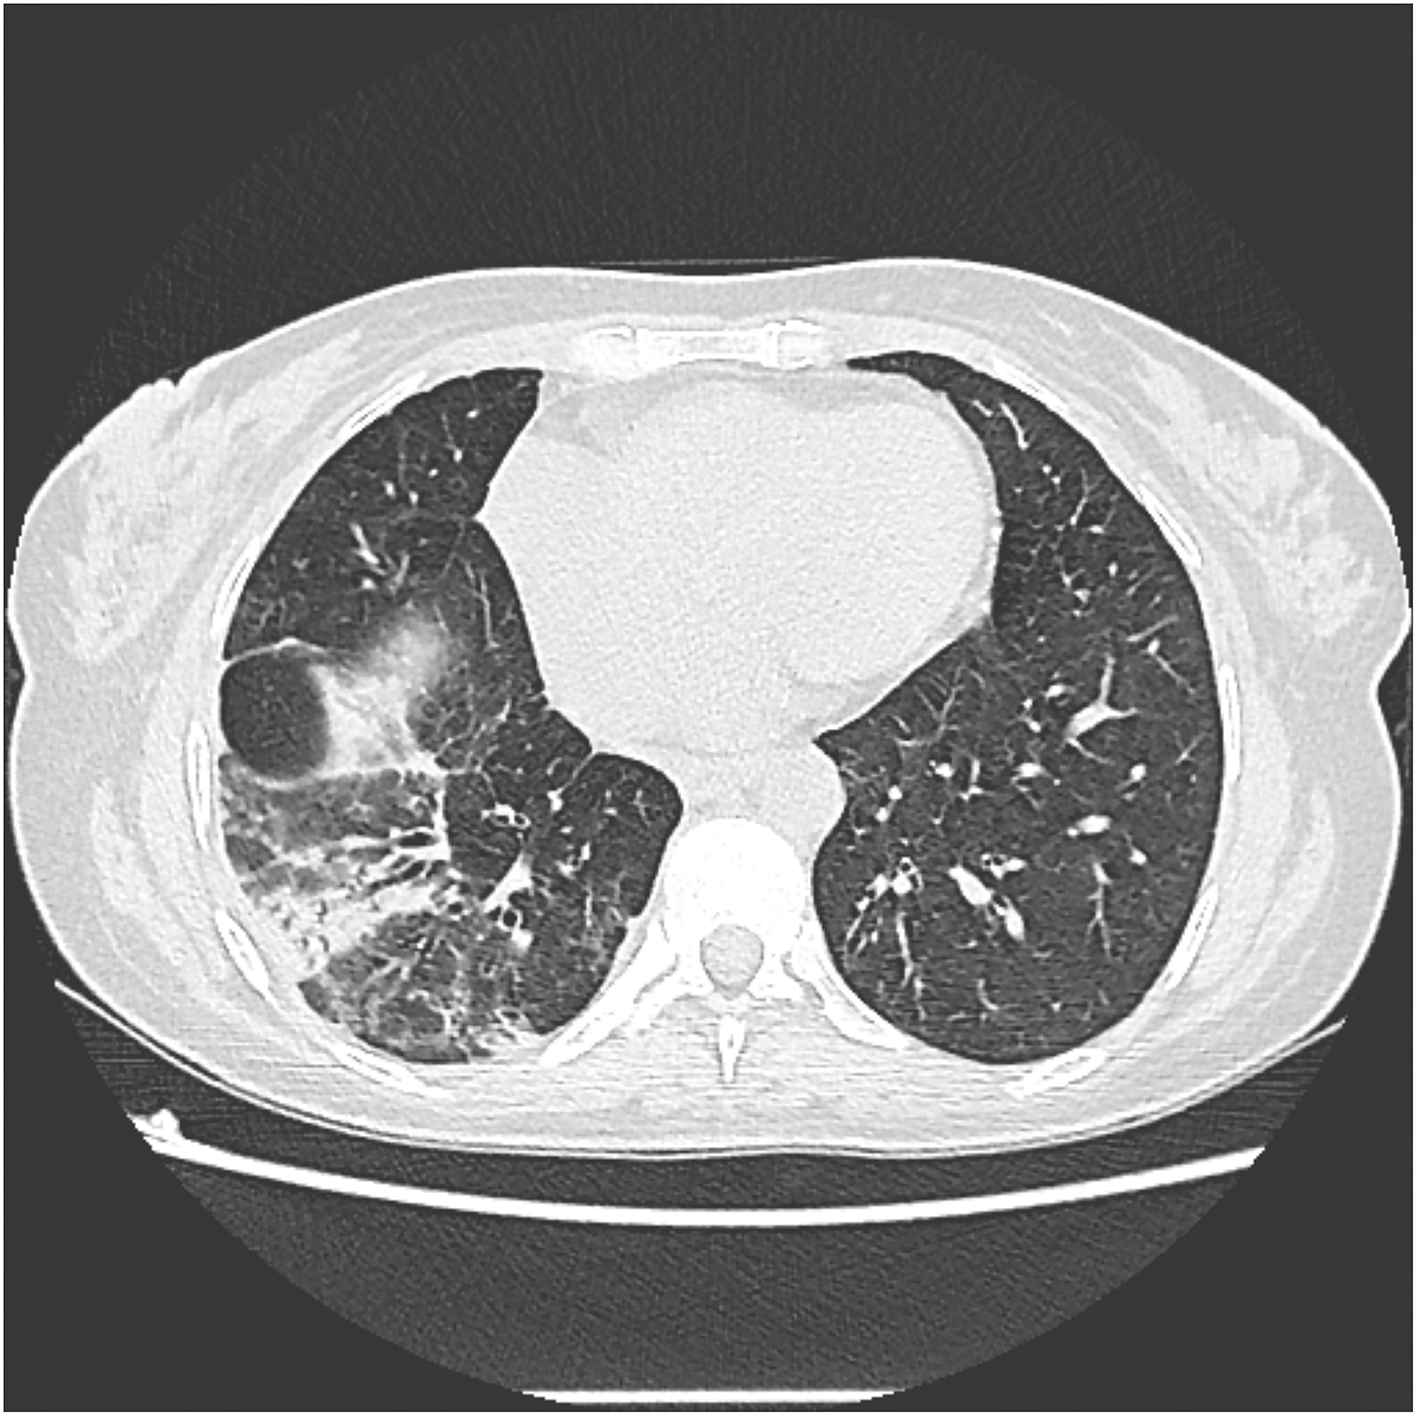

Chest and abdominal computed tomography (CT) showed a right lower lobe alveolar consolidation with air bronchograms, surrounded by opacities with ground-glass attenuation compatible with an inflammatory or infectious process (Figure 2). Moreover, the liver showed an enlarged right lobe, with chronic disease characteristics and marked dilation of the intrahepatic bile ducts, without an obstructive factor or dilatation of the hepatocholedochal duct. A biochemical analysis of the sputum showed increased conjugated bilirubin (14.4 mg/dL).

FIGURE 2

Figure 2. Slice of CT scan showing parenchymal consolidation of the right lower lobe.